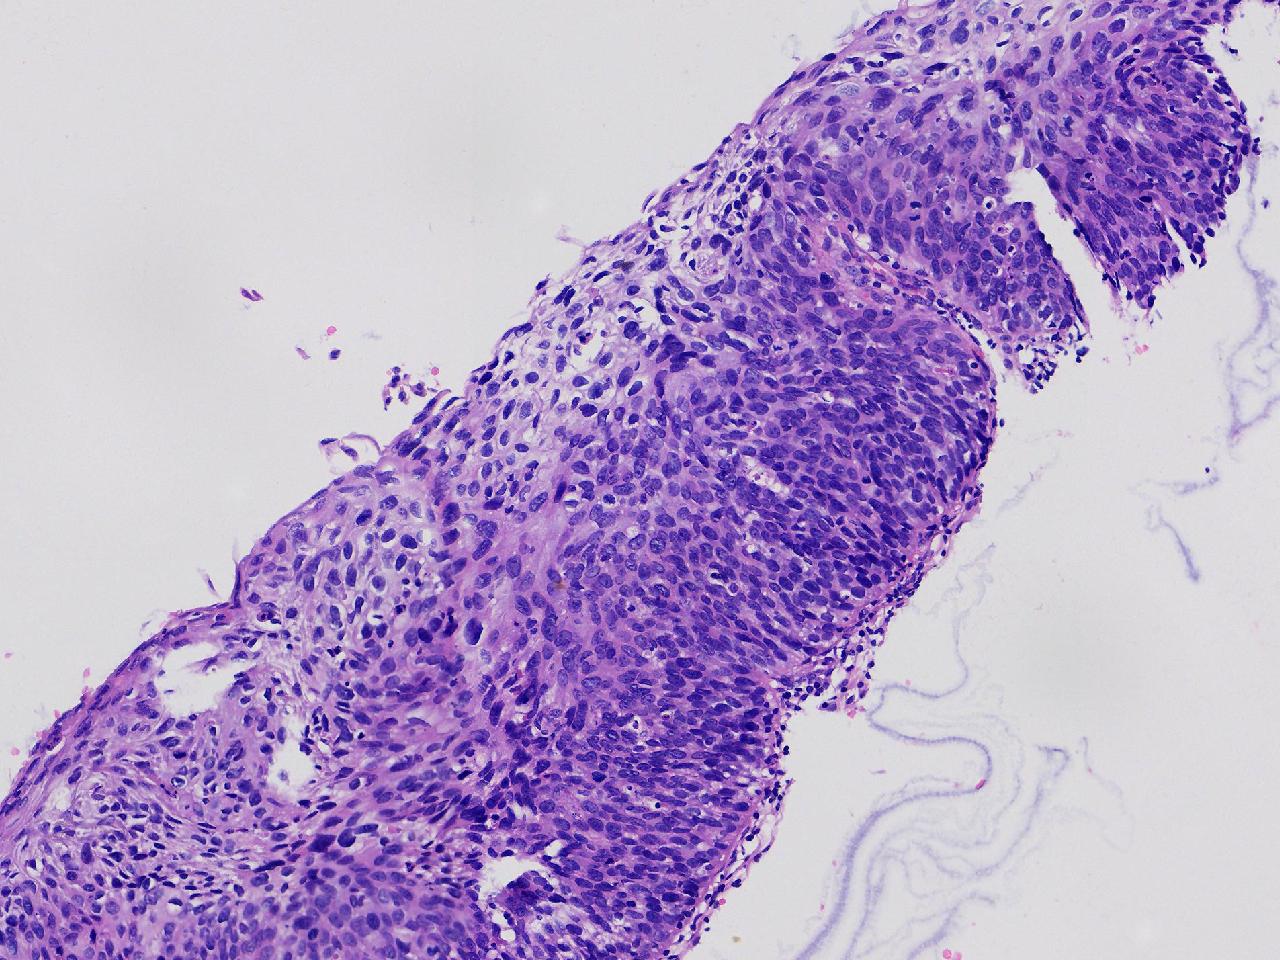

CIN2级?

女,46岁,宫颈活检。HPV16+

标本名称

宫颈活检

大体所见

宫颈多点活检。

CIN2...